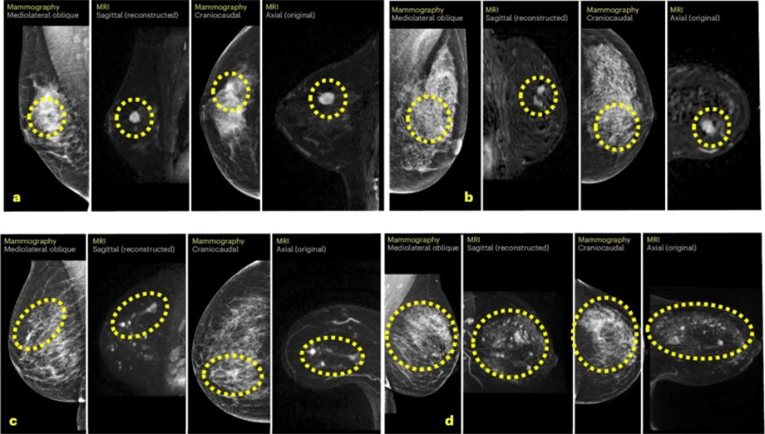

Истражувачите го користеле алгоритмот Mirai, модел на вештачка интелигенција базиран на длабоко учење, кој анализира секој мамограм и создава персонализиран трогодишен резултат на ризик врз основа на густината на ткивото и суптилните карактеристики што човечкото око не може да ги забележи.

„Нашите наоди покажуваат дека дополнителен преглед на 20% од мамограмите што ги означи вештачката интелигенција би можел да овозможи порано откривање на речиси половина од интервалните карциноми,“ изјави професорот Џошуа В.Д. Ротвел, водечки автор на студијата. „Тоа би им овозможило на лекарите на жените со највисок ризик да им понудат дополнителни методи на снимање, како магнетна резонанца или мамографија со контраст.“